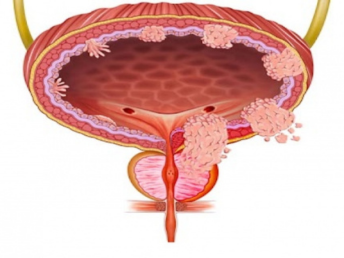

Bladder Disorders

Urologic Cancers

Effective treatment for kidney and urinary stones along with complete care for infections, obstructions, and bladder disorders.